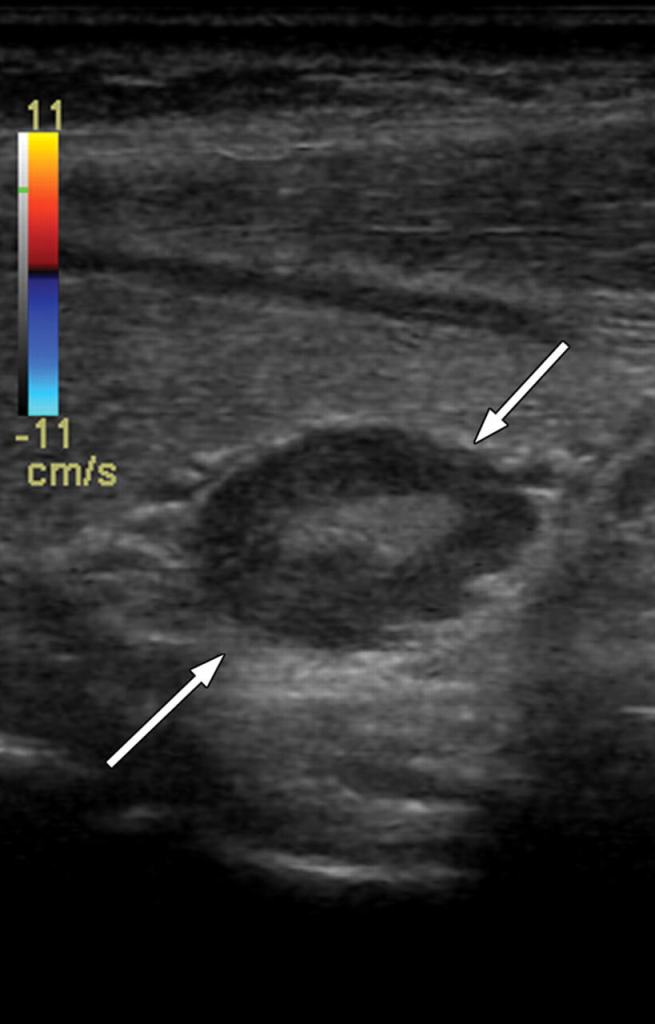

No ultrassom, as alterações patológicas das glândulas paratireoides podem manifestar-se como nódulos com formatos variados, incluindo o aspecto de feijão ou contornos multilobulados, além de alterações vasculares detectáveis ao Doppler.

No exame ultrassonográfico, alterações patológicas das glândulas paratireoides costumam manifestar-se como nódulos hipoecoicos, bem delimitados, localizados geralmente posteriores ou inferiores à glândula tireoide. Esses nódulos podem apresentar formatos variados, como aspecto de feijão ou contornos multilobulados, e muitas vezes exibem alterações vasculares ao Doppler.

O padrão de vascularização é característico: observa-se fluxo sanguíneo abundante, com arco vascular periférico e um vaso nutridor polar, geralmente proveniente de ramos da artéria tireoide inferior. Esse achado auxilia na diferenciação em relação aos linfonodos cervicais, que apresentam irrigação predominantemente hilar. Outras características que podem estar presentes incluem o aumento assimétrico da vascularização no parênquima tireoidiano adjacente e a presença de cápsula hiperecoica delimitando a lesão.

O adenoma de paratireoide costuma apresentar-se no ultrassom em escala de cinza como uma lesão homogeneamente hipoecoica em relação à tireoide adjacente, sendo mais facilmente identificado quando ultrapassa 1 cm de diâmetro. Essa característica está relacionada à alta celularidade típica da lesão.

Morfologicamente, tende a ser oval ou em formato de feijão, embora adenomas maiores possam assumir aspecto multilobulado.

Além disso, no estudo com Doppler colorido, observa-se frequentemente um vaso de alimentação extratireoideano, geralmente originado da artéria tireoidiana inferior, que penetra em um dos polos da glândula. A vascularização interna costuma ter padrão periférico, com ramificações que formam um arco característico antes de atingir regiões mais centrais.